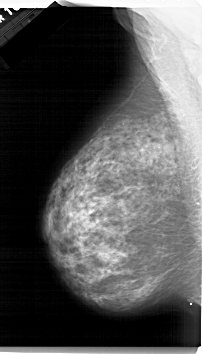

A_1315_1.LEFT_MLO

LEFT_MLO LINES 6721 PIXELS_PER_LINE 3856 BITS_PER_PIXEL 12 RESOLUTION 43.5 NON_OVERLAY